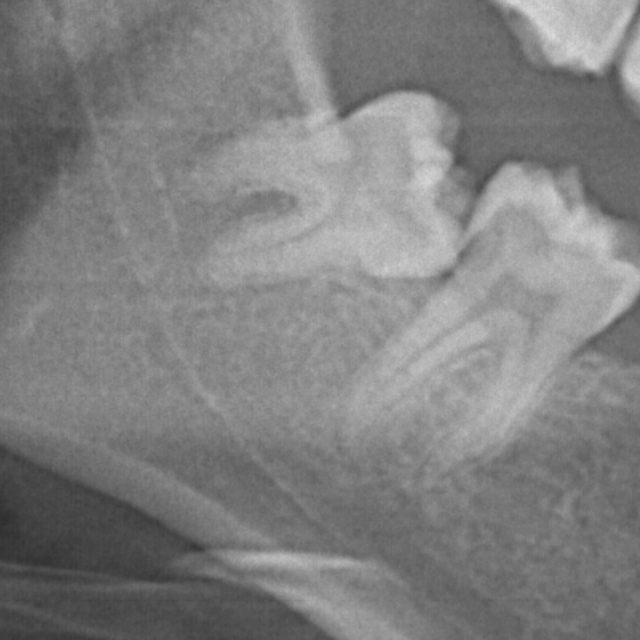

親知らず